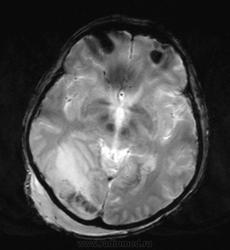

Мужчина проходит курс химиотерапии по поводу Т-клеточной лимфомы с первичным поражением кишечника (гистологическая верификация). За последний месяц - появление множественных очагов в печени, а также необычных изменений в голове.

- бесформенное образование в мягких тканях затылочной области, накапливающее контраст;

- утолщение твердой мозговой оболочки в той же области с накоплением контраста по пахименингиальному типу;

- отек прилежащей мозговой ткани с геморрагическими изменениями в коре, сопровождающийся масс-эффектом.

Мое мнение это лимфома кожи с прорастанием (если так можно сказать) через перфорирующие сосуды в ТМО, с кровоизлияниями в коре за счет повреждения сосудов. Либо это лептоменингальнаые проявления лимфомы. Больше на ум ние чего не приходит. Хотелось бы услышать мнение более опытных специалистов. но все почему-то молчат...

Я тоже думаю, что это лимфома. Думаю, не так важно, прорастает ли она из мягких тканей в мозговые оболочки, или наоборот. Только поражение мозговой оболочки - это пахи-, а не лептоменингиальные изменения.

В таком случае изменения в мозговой ткани - это отек, обусловленный нарушением венозного оттока по поверхностным венам; думаю, вкупе с геморрагическими изменениями этот отек можно квалифицировать как венозный инфаркт.